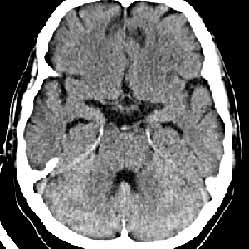

We report the case of a 58-year-old man with non-Hodgkin lymphoma of the stomach who presented with the symptoms of left-side facial palsy manifesting for three months. No generalized skeletal disease which may cause the hemifacial neuropathy and respiratory viral infections was evident. CSF analysis did not show lymphoma cells. The patients did not complain of tinnitus, vertigo, or hearing loss. No brain metastases from non-Hodgkin lymphoma could be detected by contrast-enhanced axial computerized tomography (Figure, right).

Multi-slice computerized tomography (MSCT) of the brain with 2-dimensional reconstruction showed an osteophyte of the upper wall of the left auditory meatus (size 2.4 2.2 mm) (Figure, left).

Figure. Multi-slice computerized tomography of the brain with 2-dimensional reconstruction showed an osteophyte of the upper wall of the left auditory meatus (left). No brain metastases from non-Hodgkin lymphoma could be detected by contrast-enhanced axial computerized tomography (right).